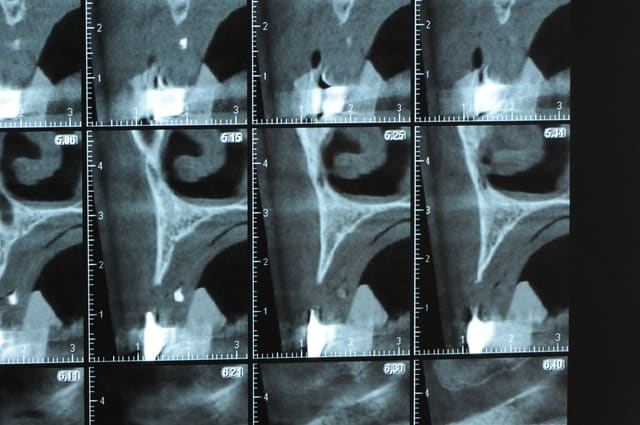

Une petite étude de ton cas D57

Sous réserves bien sur de voir l’animal en vrai

Les zones exploitables radiologiquement parlant:

Coupes implant

2,3 40100

4,96 35130 avec sinus lift mais difficile

5,25 35150

6,02 35130

6,78 35115 après réduction de hauteur de crête

7,26 35115 après réduction de hauteur de crête

8,51 35150

10,43 40115 ou 50115

11,10 40115

Ce qui nous fait 9 implants possible évidement avec un comblement de sinus on augmenterait encore les zones implantable mais ce n’est pas le but recherché, avec 8 (4+4) il doit être possible de faire une belle barre support de complet